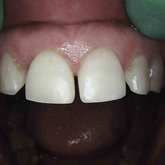

Porcelain crowns and restorations made in one appointment.

We make it a priority to incorporate the latest in dental technology in everything we do at our practice. ...